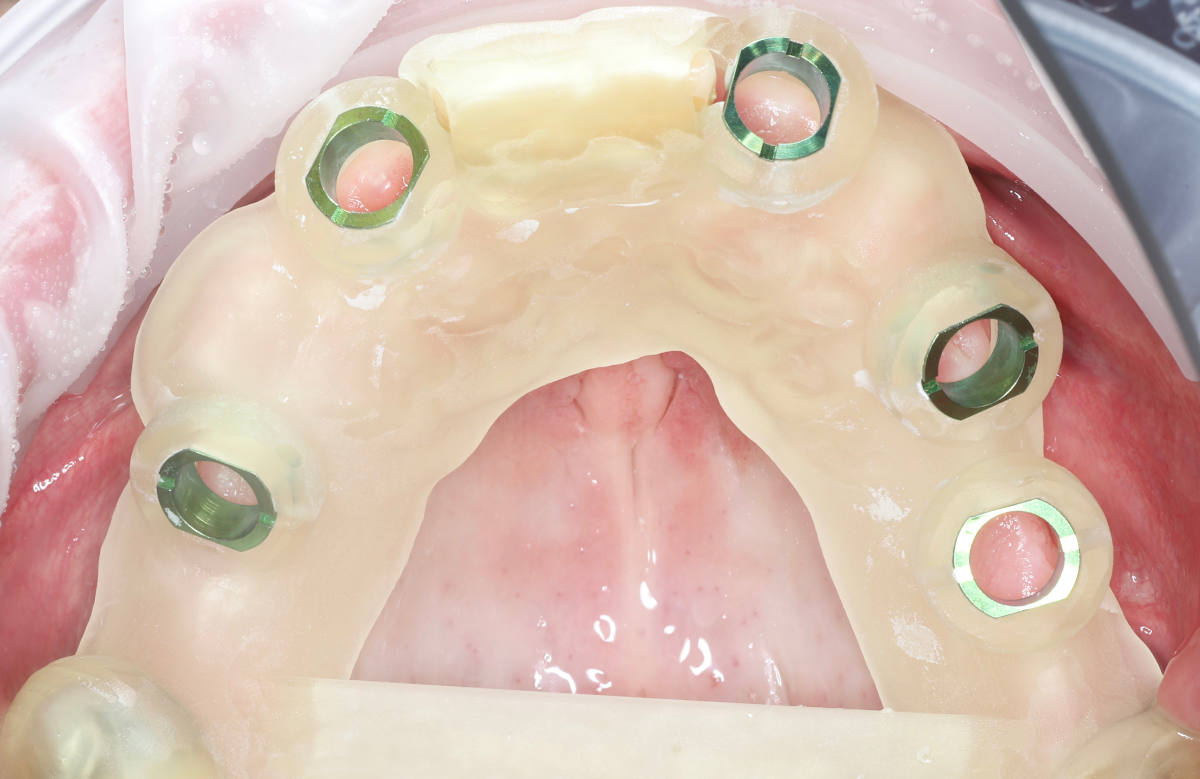

Navigovaná chirurgia, 5 implantátov

Autor práce Dr. Michal Repaši

Zubný technik Vasil Csopej